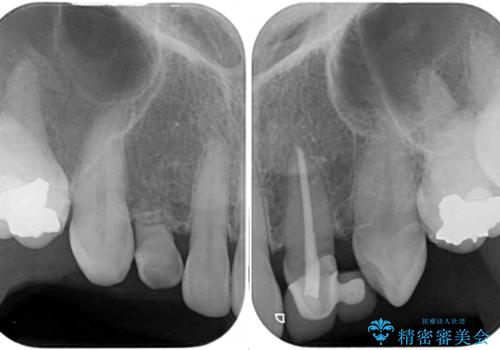

上顎は左右ともに小臼歯が欠損しており、右側は乳前歯が残っている状態でした。

ブリッジによる補綴治療にて、欠損や隙間を補完することとしましたが、神経を取り除いたり、審美的に不自然になることを避けるため、部分矯正を併用することとしました。

乳歯は事前に抜歯することとしました。